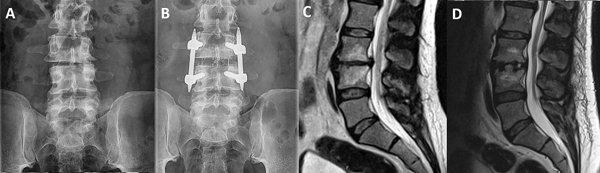

Las técnicas de fusión intersomática lumbar por vía lateral, tanto el LLIF como el OLIF, minimizan la lesión de partes blandas, acortan la estancia hospitalaria, la pérdida sanguínea intraoperatoria, a la vez que igualan o mejoran los resultados clínicos y radiológicos respecto a las técnicas por vía posterior16,17. La deformidad en los planos coronal o sagital se puede corregir empleando cajas intersomáticas de mayor tamaño y con diferentes ángulos de lordosis18. Además estas técnicas han demostrado que incrementan la altura del foramen y la superficie del canal vertebral, consiguiendo una descompresión indirecta de las estructuras nerviosas.19 (Figura 4A-D)

Figura 4: (4A-B) Radiografía pre y postoperatoria de un paciente, apreciando la restauración del espacio discal. (4C-D) Imagen de resonancia pre y postoperatoria en la que se aprecia restauración de la altura discal y retracción de la protrusión vertebral.